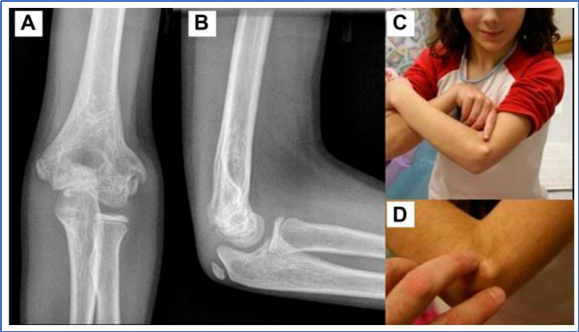

鱼尾畸形

晚期并发症,因中央骨骺闭合致肱骨髁外侧端单独生长,表现为肘关节活动受限、疼痛、关节内游离体、外翻畸形;影像学表现重于临床功能影响,无症状者仅观察,有症状者可行游离体取出、骨骺融合、肱骨远端截骨。

外侧骨赘

骨折愈合后,患儿常出现明显的外侧骨性隆起增生。作者强烈建议,临床医生应在启动治疗之初,即告知家属患儿术后可能出现外侧骨性隆起,而非待隆起形成、引发家长焦虑后再做解释。

图20: 一名 9 岁 8 个月女童,1 年 9 个月前因肱骨外髁韦氏 Ⅲ 型骨折接受切开复位内固定术A 正位 X 线片可见肘部外侧形成明显骨性隆起(骨棘);B 侧位 X 线片显示该骨性隆起无明显向前、向后延伸;C 患儿指认肘部外侧骨性隆起的临床照片;D 医师指认该骨性隆起的临床特写照片;该骨性隆起仅予临床观察随访,未行手术干预。